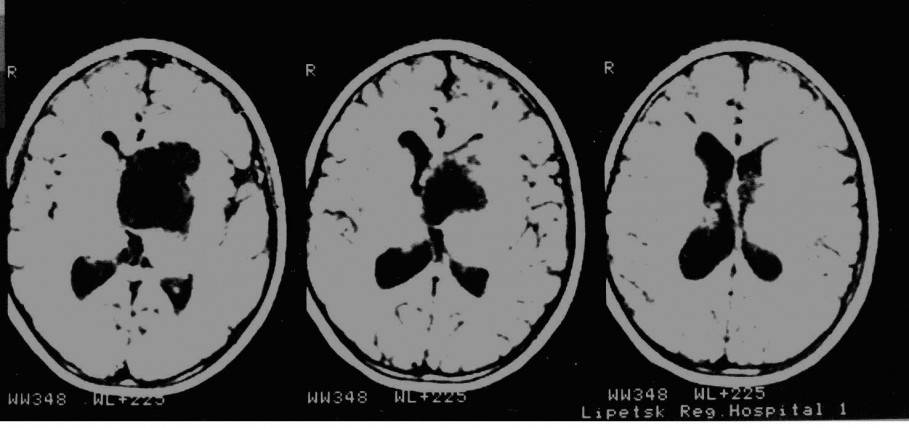

На представленных томограммах у девочки 10 лет имеет место обширная киста хиазмально-селлярной области, затрудняющая отток ликвора через отверстия Монро и вызывающая окклюзионную гидроцефалию.

Под УЗ контролем выполнена пункция кисты через отверстие Монро с последующей ее катетеризацией и имплантацией резервуара Омайя. На последующих томограммах подтверждается точность установки катетера. Гидроцефалия значительно уменьшилась.

В дальнейшем производились регулярные( 1 раз в месяц) пункции резервуара, что обеспечило купирование гидроцефалии. Ребенок посещает обычную школу. Контрольные МРТ спустя год. Видно, что киста сохраняет свой объем, но гидроцефалия купирована.